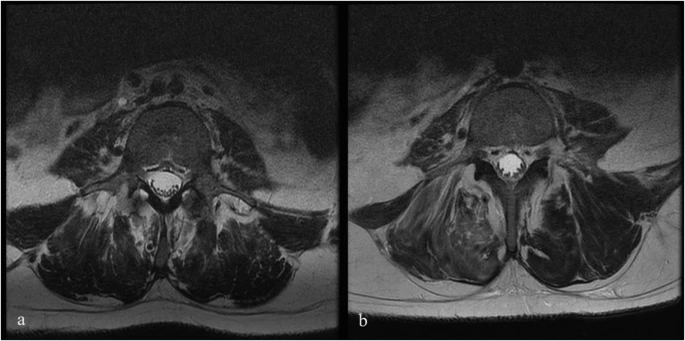

注射后血液和腦脊液檢查未發現異常。隨訪時MRI未見明顯變化;然而,在十名患者中,有八名檢測到馬尾神經根的叢集輕度增加,有或沒有結節性增強的證據。在經歷馬尾神經根聚集或強化的患者中,沒有發現明顯的臨床相關性。圖1顯示了患者6的輸注前和隨訪MRI,該患者L4-S1水平的馬尾神經根叢集輕度增加。表3突出顯示了所有患者干細胞注射前后的MRI變化。三名患者的SSEP有所改善。兩名患者與基線相比沒有任何變化,四名患者無法進行解釋,一名患者在整個研究期間具有正常的SSEP。表4突出顯示了SSEP 的發現和解釋。